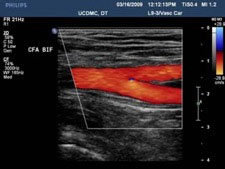

Peripheral artery disease (PAD) is usually diagnosed based on patients’ symptoms and physical examination in the clinic, confirmed by ultrasound evaluations in the Vascular Laboratory with pressure measurements and other non-invasive tests.

Ultrasound duplex scanning can provide additional information that may guide therapeutic decisions. The location and severity of arterial narrowing and occlusions can be identified. The vascular technologist can map disease in lower-extremity segments with high accuracy — though duplex scanning is more time-consuming than other lower-extremity arterial studies.

The additional information from duplex scanning can help determine if the arterial disease might be appropriately treated with endovascular intervention. The type of treatment and the technical approach can be guided by the duplex scan findings. Information from the duplex scan can help patients be better informed about their options. Duplex scanning after intervention can provide objective information about the success of the procedure, and serial follow-up examinations can identify recurrent problems at an early stage, sometimes prompting follow-up interventions.

Some preparation is needed. A complete lower extremity arterial evaluation includes duplex scanning of the aorta and iliac arteries in the abdomen and pelvis. Gas in the intestinal tract can interfere with ultrasound evaluation. It is, therefore, best to have the examination performed after an overnight fast and it is essential to avoid tobacco and caffeine before the test. A complete study can take up to 30 minutes.